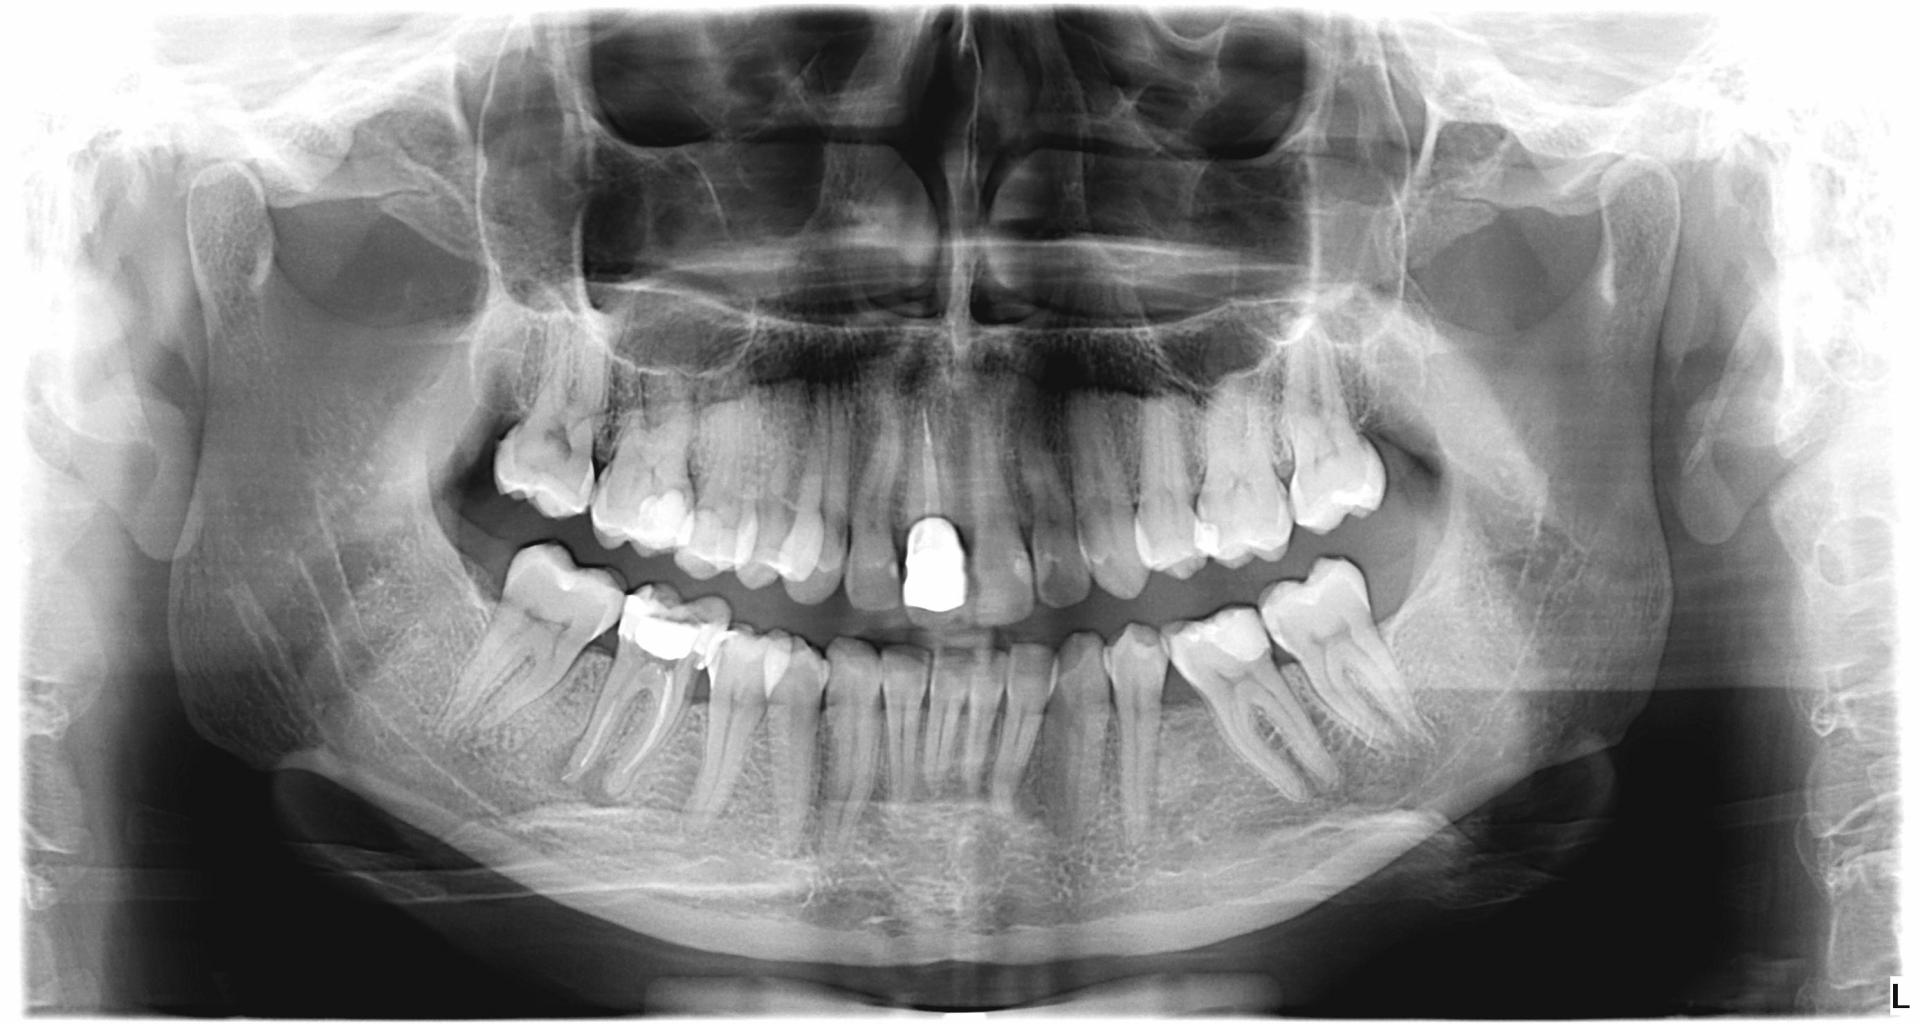

У нашому кабінеті ми знімаємо зуби за допомогою цифрової рентгенографії. Даний тип пристрою видає зображення на екрані монітора вже через кілька секунд після його виконання. Доза опромінення в кілька разів нижча, ніж у традиційних аналогових рентгенівських апаратах, що робить обстеження набагато безпечнішим.

- Панорамне фото